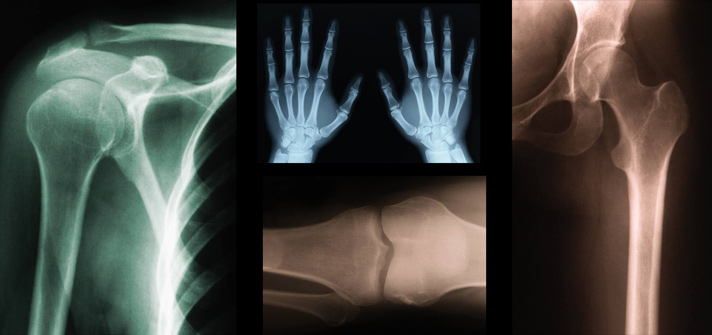

Chronic inflammatory diseases of joints are major causes of disability in the ageing population. Osteoarthritis (OA) is one of the most common types of arthritis and a major cause of pain and disability in older individuals. OA is expected to place a heavy burden on European healthcare systems, as European citizens grow older.

Cartilage damage in OA is detected radiographically by decreases in joint space width (JSW). However, radiographic evidence is seen only after significant cartilage degradation has already taken place. The early stages of the disease may remain latent and asymptomatic for many years.